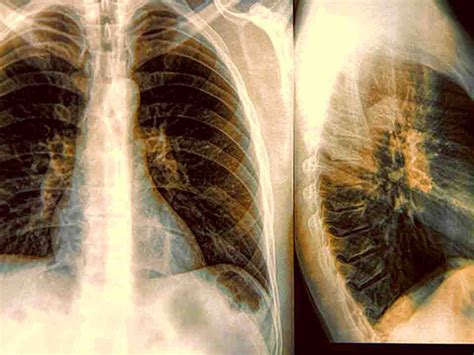

哎呀,说到继发性肺结核,这可不是什么小感冒,能自己偷偷好起来那种!我有个朋友,刚开始也是满不在乎,觉得身体强壮得很,这种病怎么可能找上他。结果呢,咳咳咳,咳得他晚上都睡不好觉...

浏览:141 时间:2024-08-19 点击阅读